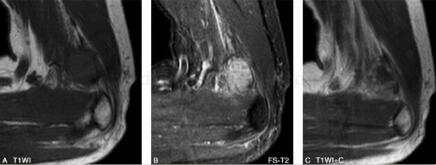

图3

(二)MRI

MRI能够直观地显示滑膜肉瘤的病灶形态、范围、与相邻关节、肌腱、滑膜及骨骼的关系。瘤体多表现为不规则,边缘呈分叶状,有时可见较清晰包膜。由于肿瘤常见囊变、出血、坏死以及钙化,因此MR信号不均。肿块内部的信号特点与其病理组织成分密切相关,T1WI上,肿块实体部分与周围肌肉信号相比表现为中等稍高信号,瘤体内的出血灶表现为点片状高信号,坏死或钙化区则表现为更低信号;

相应的T2WI上肿块实体部分表现为较高信号,坏死灶信号更高,钙化区表现为低信号,出血灶则信号不一,有时可见液-液平面;滑膜肉瘤较具特征性的MR表现是T2WI抑脂序列中,肿瘤表现为结节状稍高信号,结节呈大小近似的“卵石”状,其间有粗细不等的条状、网格状低信号间隔;增强扫描显示病灶不均一显著强化,病理证实系肿块内部含有丰富血窦。